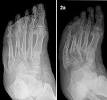

Charcot fu : Italienisch Deutsch PONS Übersetzungen für charcot fu im Italienisch Deutsch-Wörterbuch von PONS. Charcot-Fuß Der Charcot-Fuß ist eine Erkrankung des Fußes, bei der Knochen schnell brechen, ohne dass die Betroffenen Schmerzen empfinden. Der Charcot-Fuß ist eine Erkrankung des Fußes, bei der Knochen schnell brechen, ohne dass die. Online:fu, il fu Giuseppe Bianchi, Bianchi Mario fu Giuseppe. Ich habe mal gegooglet und das gefunden.

Ausschlussdiagnose und nicht immer leicht zu erkennen. Charcot Fuß Wörterbuch Spanisch-Deutsch Übersetzung für Charcot Fuß im Spanisch-Deutsch-Wörterbuch. Häufig und häufig unerkannt: Charcot-Neuroarthropathie Medscape 9. Diabetisches Fußsyndrom (Charcot-Fuß) - Universität zu Lübeck Diabetisches Fußsyndrom (Charcot-Fuß). (Schmerzen, Füße, Diagnose) Charcot-Fuß Der Charcot-Fuß ist eine Erkrankung des Fußes, bei der Knochen schnell brechen, ohne dass die.